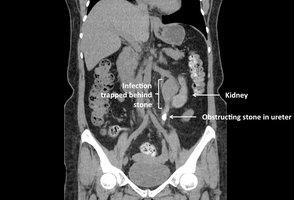

Renal Calculi (Kidney Stones): Calcium deposits causing obstruction; treated with lithotripsy.